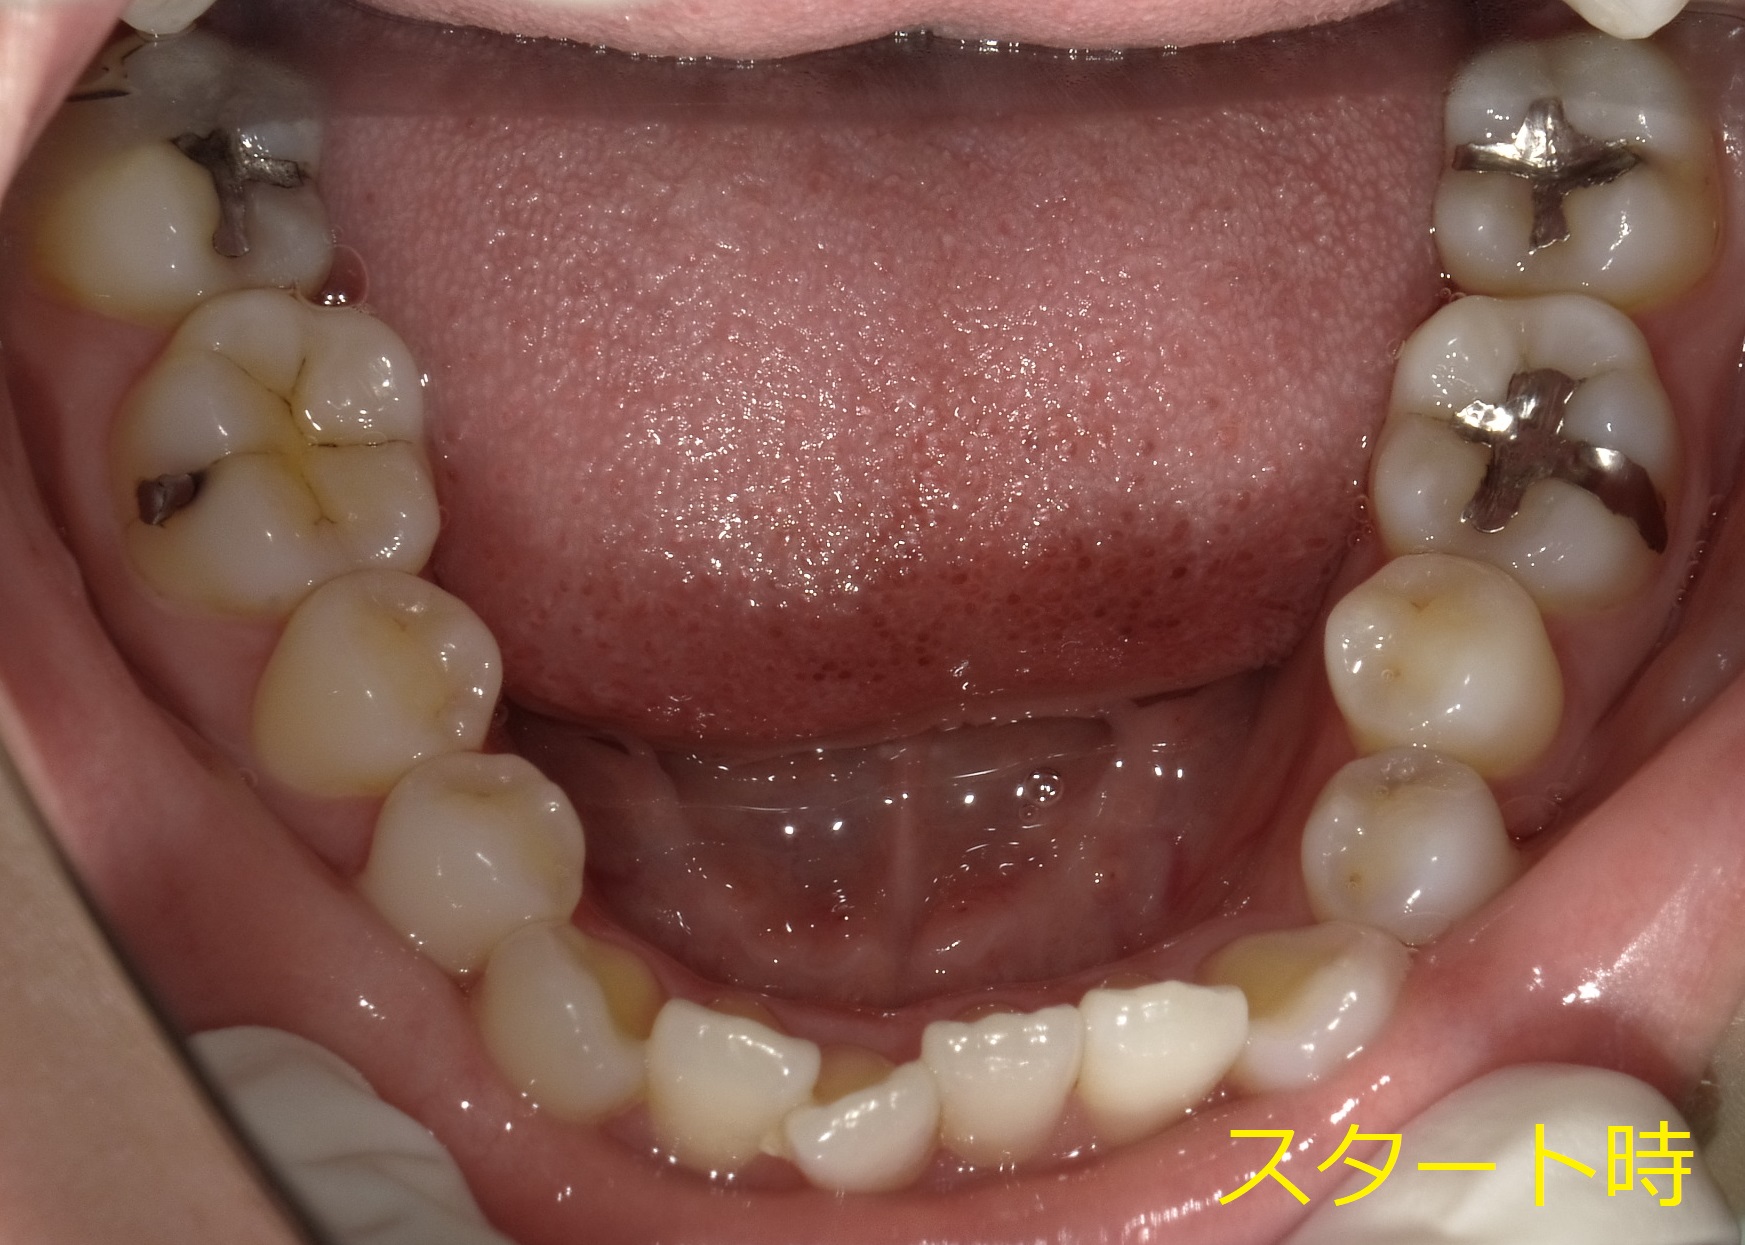

横からの写真です。

横から見ると、前歯が内側に倒れこんでいる+歯茎が出ていることによる存在感(前歯の根っこが出ているため)が確認出来ます。

まず最初の一か月は抜く予定の歯の側面を少し削り(痛みはないです)、そのスペースを使って歯並びを整えつつ、抜く予定の歯を動かすことで抜歯しやすくしていきます。